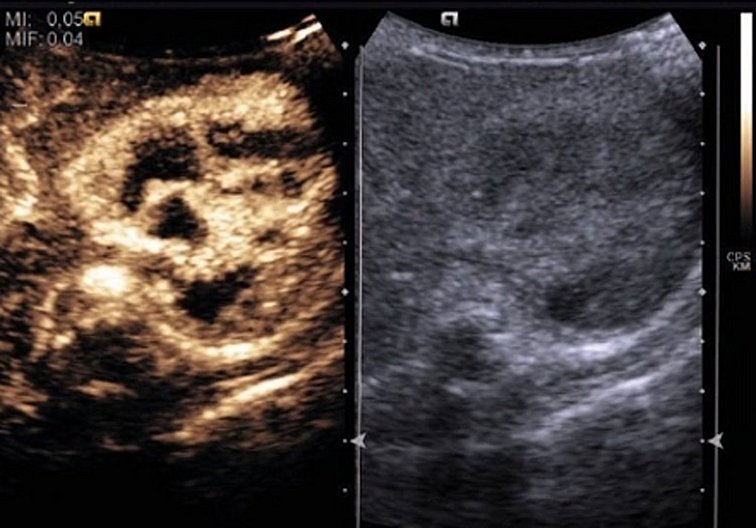

Translationale Pädiatrie versucht Erkenntnisse aus der Grundlagenforschung möglichst schnell in die Patientenversorgung zu integrieren. Unsere Abteilung ermöglicht den engen Austausch von theoretischer Medizin, patientenorientierter Forschung und Patientenversorgung. Dabei bringen wir die Disziplinen Kinderheilkunde und Jugendmedizin mit Immunologie und Physik zusammen und neue diagnostische Strategien für unsere jüngsten Patienten zu erforschen. Ein besonderer Schwerpunkt ist die funktionelle und molekulare Bildgebung.

Die Translationale Pädiatrie möchte ein neues funktionelles und molekulares Verständnis für Krankheitsprozesse entwickeln und gleichsam hierfür Diagnostik etablieren. Zentrales Element ist die schnelle Übertragung der Forschungsansätze in klinische Anwendungen. Die Forschung ist daher insbesondere auf die funktionelle und molekulare Bildgebung für Kinder- und Jugendliche fokussiert.

Im Rahmen des “Fast Track of Innovation” Programm ist EUPHORIA ein von der Europäischen Kommission gefördertes Projekt, welches sich zum Ziel gesetzt hat, außergewöhnlicher wissenschaftlicher Forschung den Übergang zur Markteinführung sowie den Einzug in Kliniken zu ermöglichen. EUPHORIA nutzt eine neue Imaging-Technologie – Multispektrale Optoakustische Imaging-Tomographie, kurz MSOT – und verbessert dessen Sensibilität und Effektivität. Das Projekt wird mit Hilfe der fortgeschrittenen Technologie von MSOT neue Wege aufzeigen, um chronisch-entzündliche Darmerkrankungen (CED) besser zu handhaben.